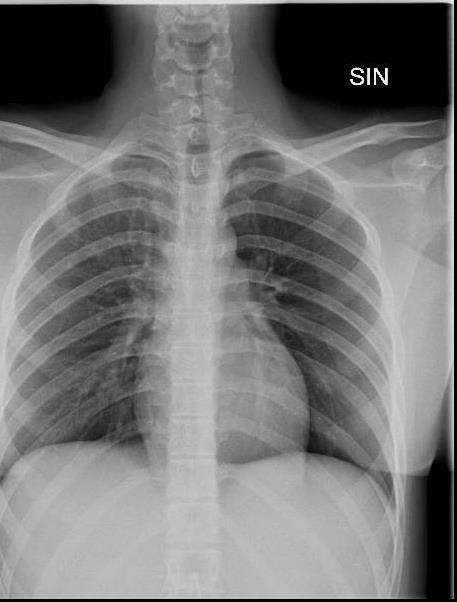

Imaging of Covid 19 infection in children CXR 8 38% 3% 51% 8%

Consolidation 35%

Collapse 3%

PeriBronchial thickening

51%

Hyperexpansion 7%

Effusion 4%

Imaging of Covid 19 infection in children CXR 9 C O V I D

Birmingham

Covid 19 CXR Imaging of Covid 19 infection in children

Lung Disorders CXR

COVID 19

• Patchy bilateral GGO, Consolidations or both

• Peripheral and lower lung zone predominance